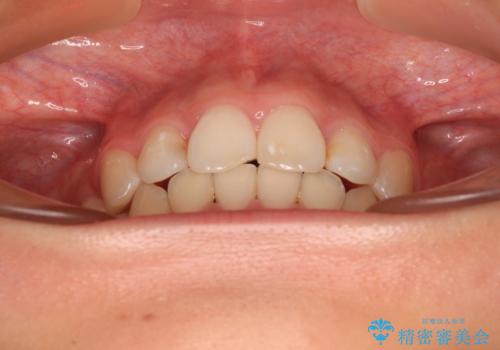

- 咬み合わせと、前歯のデコボコや八重歯、飛び出した口元を気にして来院された患者様です。

上顎は歯列不正が強く、右側臼歯部の咬み合わせは歯1本分ずれている状態でした。